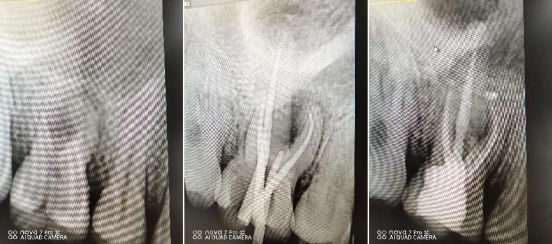

阻生牙微创拔除术

现代根管治疗术